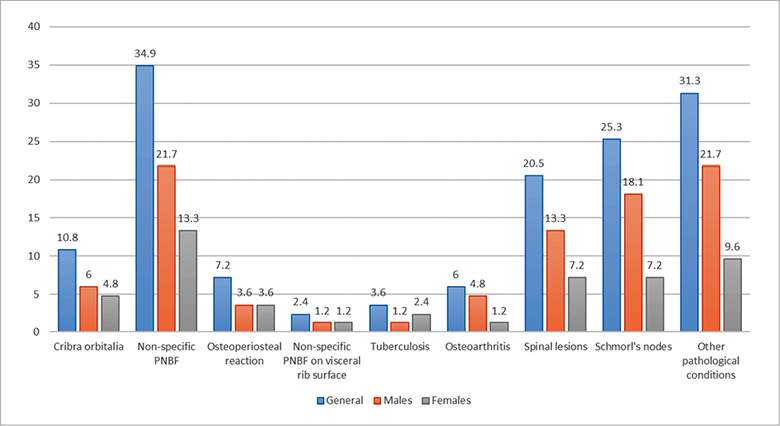

The results of the paleopathological examination are presented for non-adults and adults in Fig. 5. Crude prevalence rates (CPR) of pathology in non-adults (in %).

5 pav. Patologijų pasiskirstymas (%) nesuaugusiųjų grupėje. and Fig. 7, respectively. A total of 113 individuals (74.8% of the total sample) had at least one pathological condition. Non-adults demonstrated more pathological cases than adults – in total 48 cases (42.5% of total pathological cases), including non-specific stress markers and metabolic bone disorders (Fig. 5).

As well as for non-adults, PNBF had the highest rate in the adult group (21 cases or 25%), mostly affecting the tibia, though the rates of osteitis and osteomyelitis accounted only 1%–4% of all cases. The rate of cribra orbitalia in the adult sample was low (only 9 cases or 11%), but recorded in both males and females (Fig. 7). Three cases of tuberculosis (4%) were also diagnosed. No cases of syphilis or leprosy were observed in the Subačius Street 41 material.

Fig. 7. Crude prevalence rates (CPR) of pathology in adults.

Although degenerative joint diseases (DJD) are generally accepted as a pathological condition of multifactorial aetiology (Weiss and Jurmain, 2007), most regard it specifically as an age-related phenomenon, which is the result of continuous mechanical loading of the joints or spine throughout the lifetime of an individual (Rogers and Waldron, 1995; Larsen, 2015). Findings from Subačius Street 41 indicated that age was a significant aetiological factor of DJD prevalence for both males and females. Males were afflicted by the disease more than females in the knees (osteoarthritis) and spine (osteochondrosis and spondilioarthrosis) (7 females and 12 males). Males also suffered from Schmorl’s nodes – out of 21 cases, 15 were in the male group. Schmorl’s nodes are formed when damage to the vertebral endplate compresses the intervertebral disk, the anulus fibrosus is weakened, and the nucleus pulposus protrudes through the fibrous capsule.